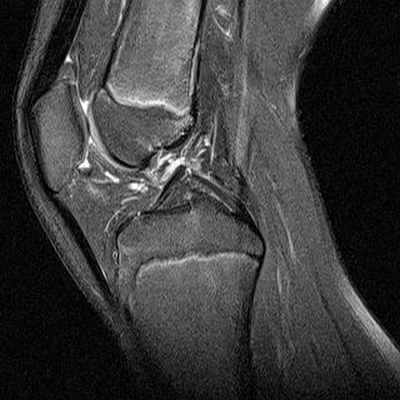

На снимке – разрыв крестообразной связки и мениска вследствие травмы колена

Для диагностики важна еще и форма мениска. В норме он в определенной плоскости имеет форму бабочки. Любые отклонения могут указывать на возможный разрыв.